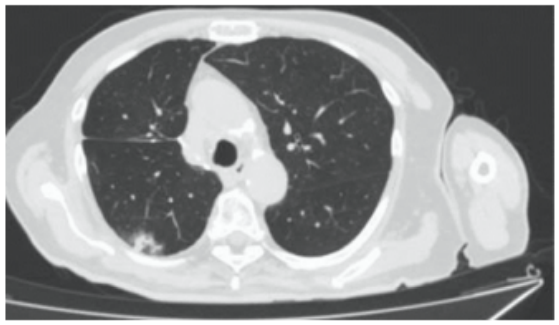

Paciente do sexo masculino, 74 anos de idade, tabagista 50 maços/ano, apresenta dispneia

progressiva e tosse crônica há 4 anos, relato de 3 descompensações nos últimos 8 meses

(piora da tosse, expectoração e dispneia), evoluindo com síndrome consumptiva há 6 meses.

Realizada TCAR com o seguinte achado:

Quais seriam hipóteses diagnósticas mais prováveis de acordo com os achados de imagem?

Quais seriam hipóteses diagnósticas mais prováveis de acordo com os achados de imagem?